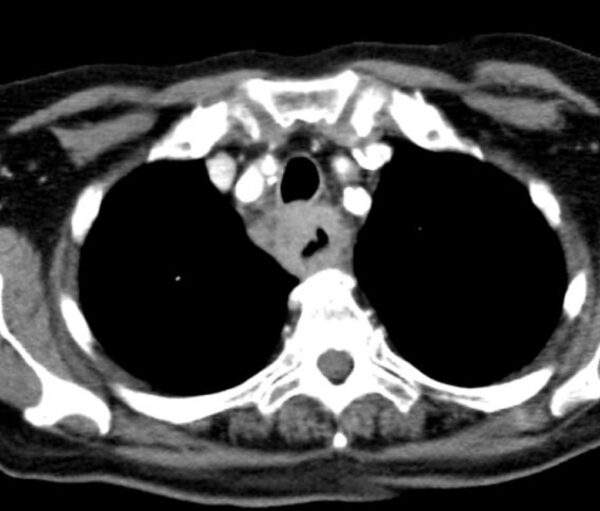

Case 16

https://radiopaedia.org/cases/oesophageal-cancer

CT

GIT